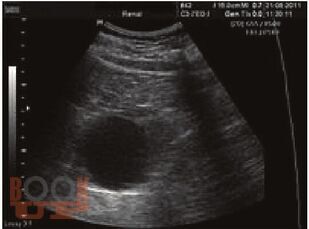

Учебное пособие предназначено для студентов лечебного, стоматологического и педиатрического факультетов, ординаторов для углубленного изучения основ хирургии, а также для врачей практического здравоохранения. В пособии дано представление о хирургической инфекции, основных актах, регулирующих правила профилактики и лечения внутрибольничной инфекции, основных видах хирургической инфекции, методах и принципах диагностики и лечения.